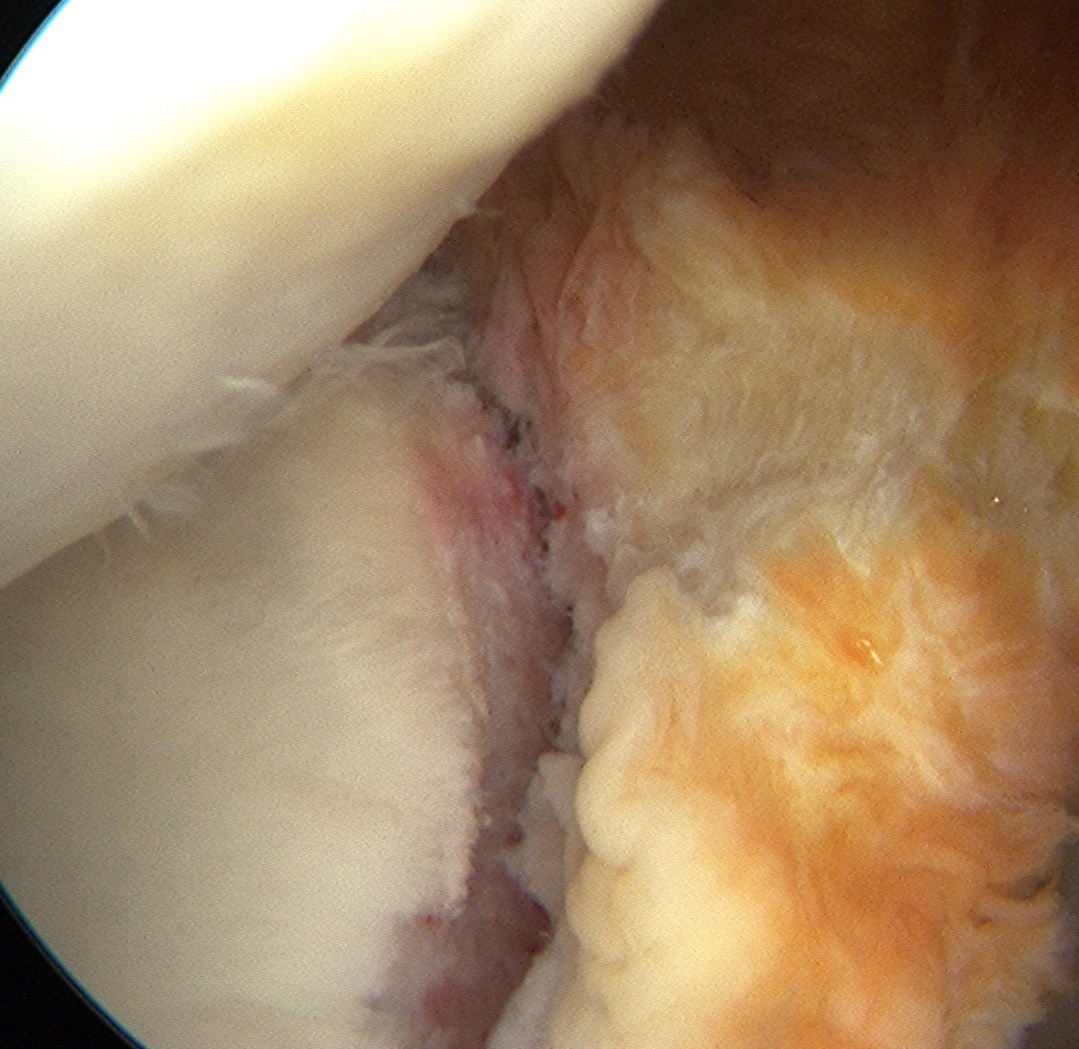

Mobilize labrum

Shoulder Scope Bankart RaspShoulder Stabilisation Labral Mobilisation

Labral mobiliser / rasp

- labral tear can be obvious, but may have partially healed or healed medially

- change camera to anterosuperior portal for better view

- mobilize until can see subscapularis muscle underneath

- need to be able to advance labrum medially and superiorly for repair

Shoulder Arthoscopy Bankart MobilisationShoulder Scope Bankart Mobilisation

Shoulder Stabilisation Anterior Labral MobilisationShoulder Stabilisation Anterior Labral Mobilisation 2